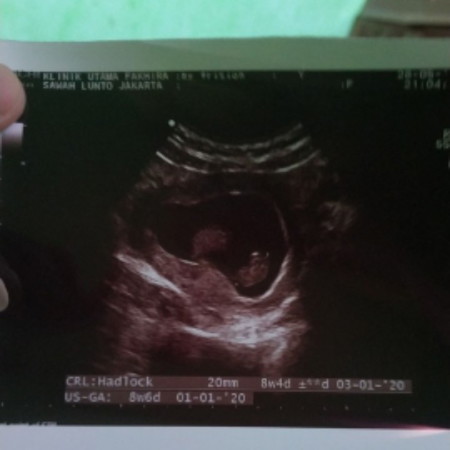

bu saya hamil 8 minggu setiap makan slalu keluar bun sudah coba minum hydromama juga bun masih tetap di kasil b6 vomil sama b6 bidan juga gak mempan bun ada gak bunda bunda kaya saya maboxnya parah apalagi mau mudik tips na n ya bun ini hamil yg ketiga bun mohon sharingnya bun